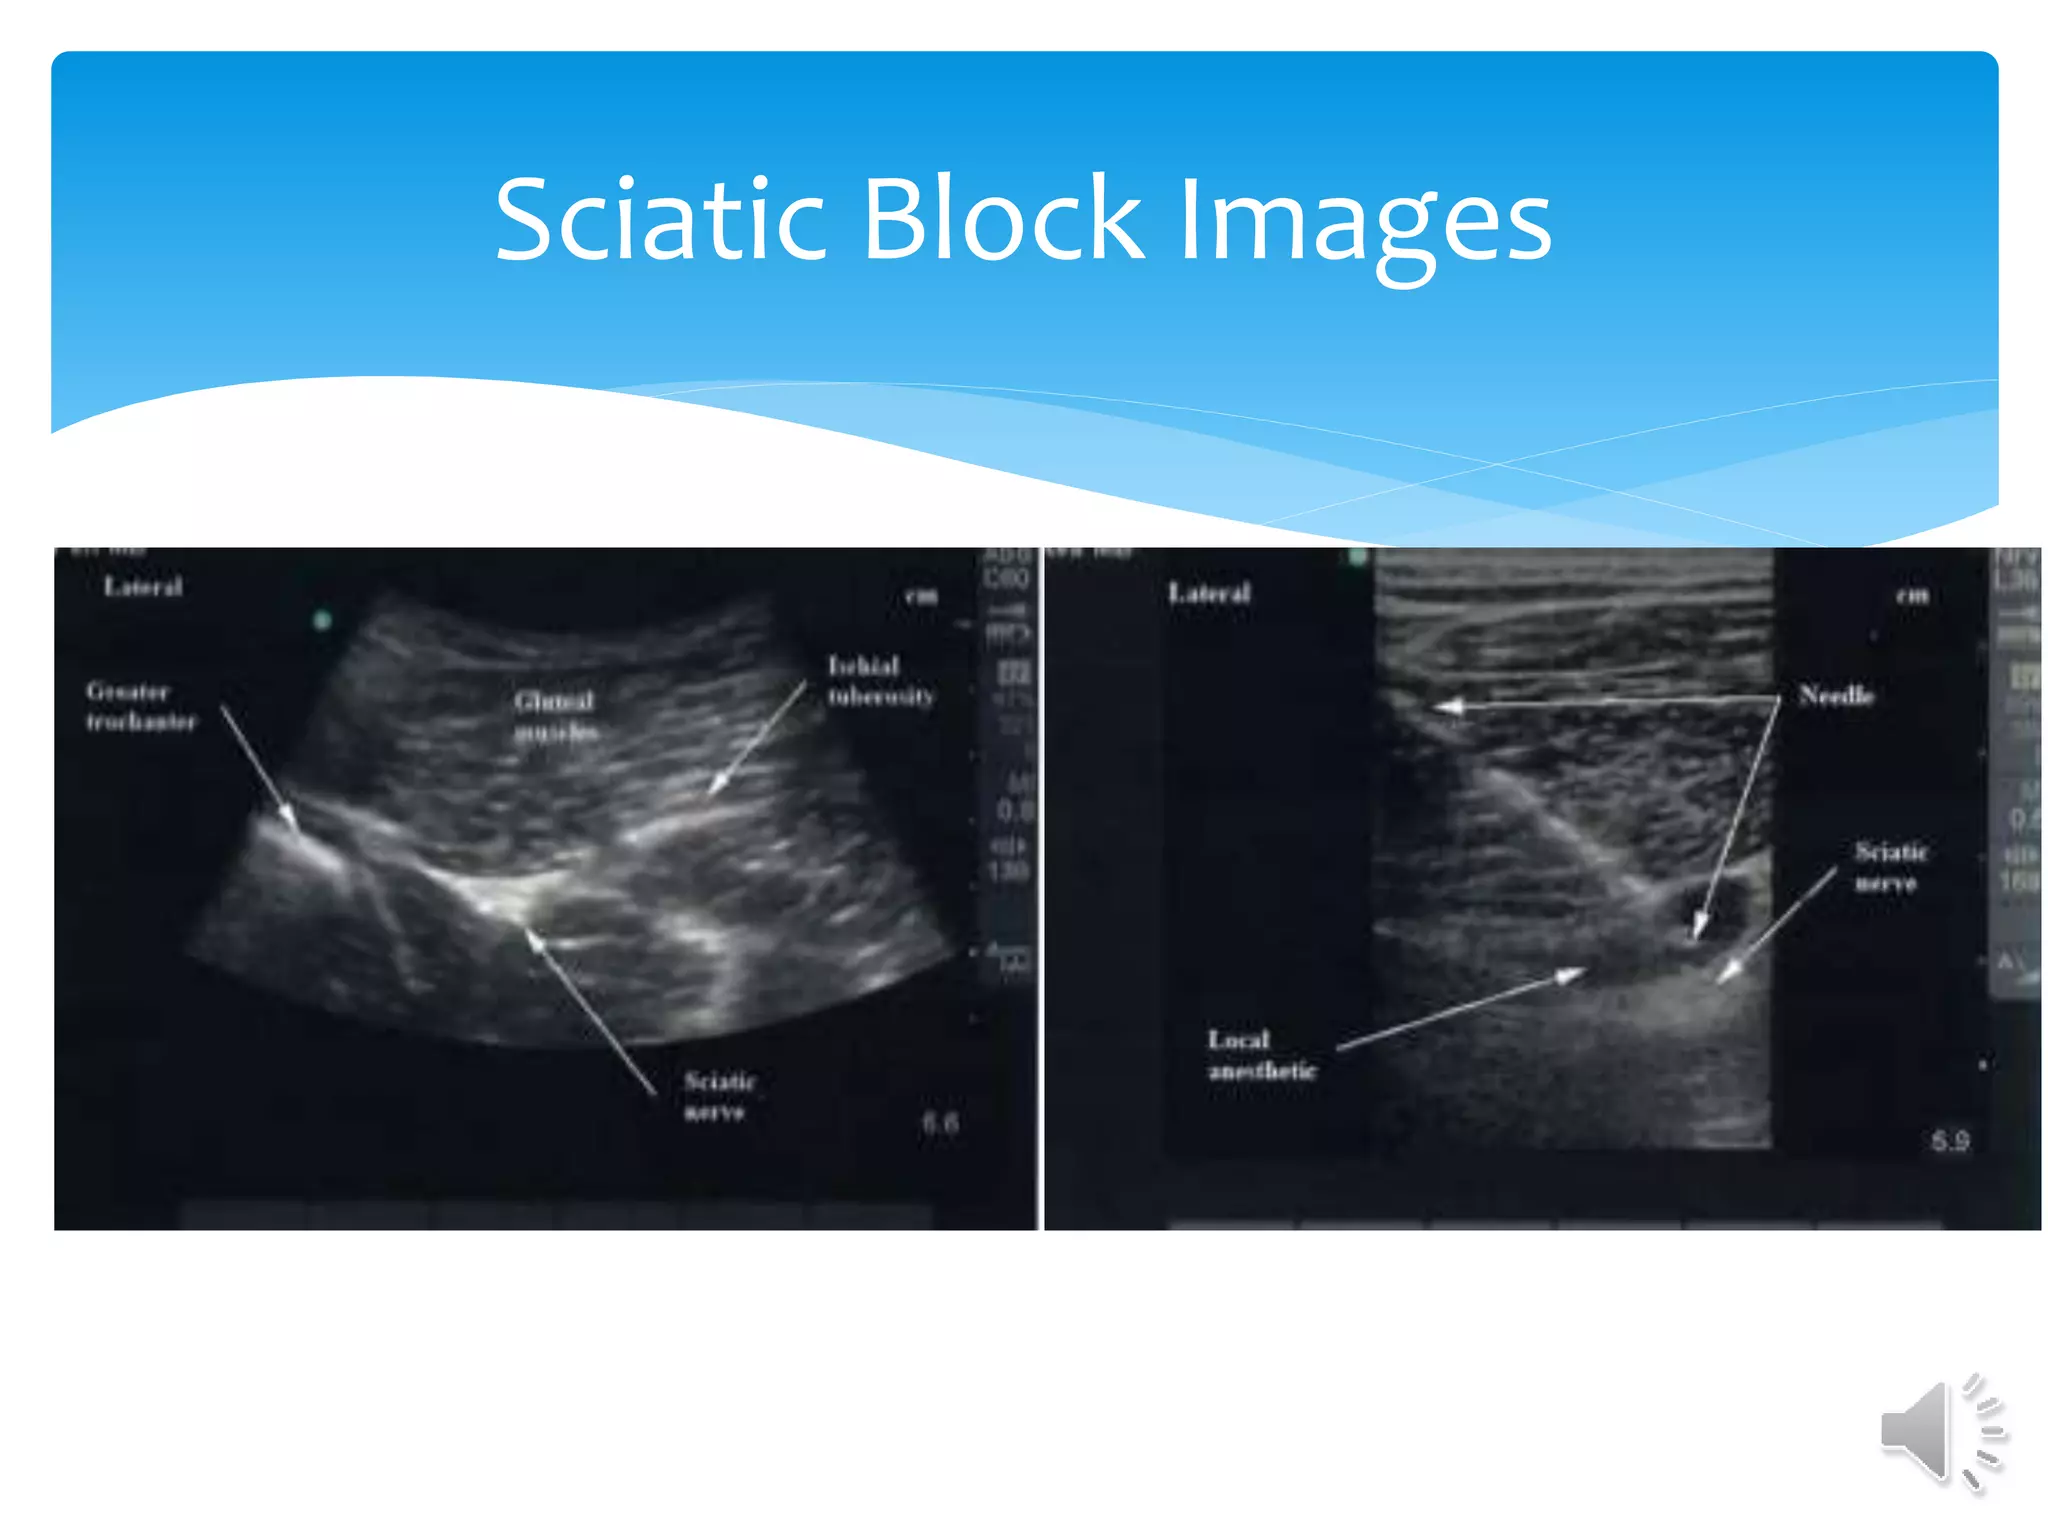

Sciatic Nerve Block

Sciatic Nerve Block Technique

Sciatic Block Images

 Large Hyperechoicnerve.  Primarily blocked for procedures knee and long bones of the lower extremity.  Can be accessed at popliteal fossa ankle procedures. Sciatic Nerve Block

• #37 Line between the greater trochanter and the ischial tuberosity. Sciatic nerve bisects this line. Large curvilinear probe for wide angle view and deeper structures.

• #38 Nerve is located between anterior surface of the gluteus maximus and posterior surface of quadratus femoris muscles. Needle direction lateral to medial. High Frequency curvilinear probe

• #39 Note lateral to medial approach to avoid vascular structures. Attempt as high as possible to ensure getting both branches of the nerve Normally used in conjunction with saphenous or adductor canal block